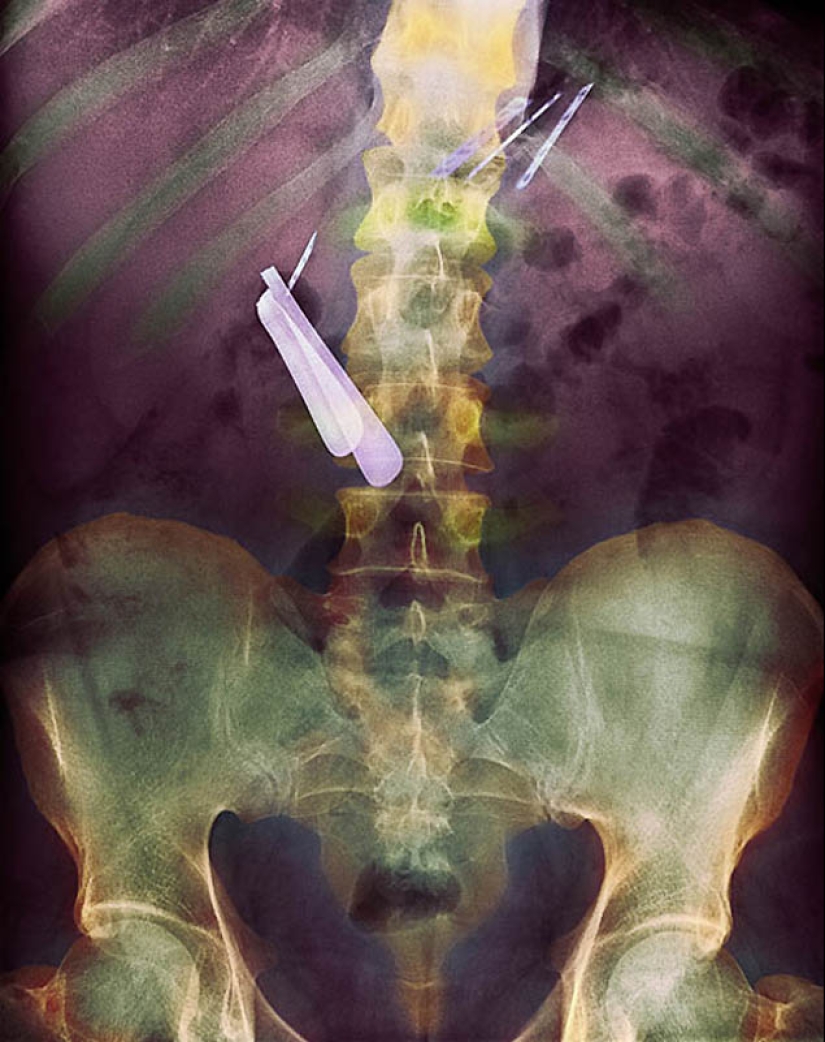

8. Color X-ray of the stomach of the patient who swallowed the razor (center left) and the blade (top right).